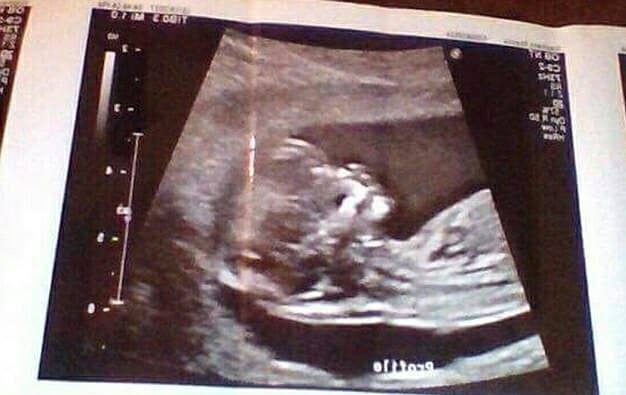

但瑞安娜無畏陌生人的言語,大膽站出來反擊說道,「我的寶寶每個月都會像其他人一樣,每個月都會長大,所以和我寶寶的健康毫無關」,雖然常要面對人們的言論,而每次都會因為這些話語而受傷,但她還是盡量保持冷靜,「因為我知道我和我的寶寶都很健康」,為了讓大家知道肚子小但孩子還是健康地,她大方出示寶寶的超音波以資證明。

▼瑞安娜分享自己健康孩子的超音波照(圖/Brad Mulcahy臉書)